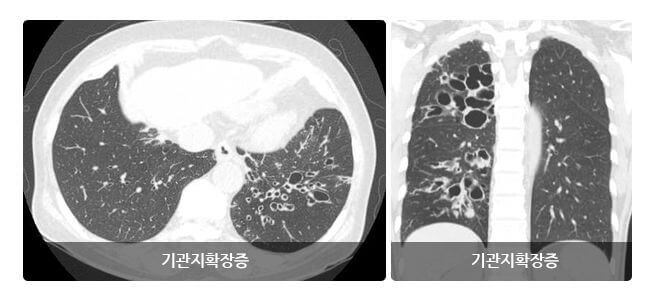

1. 기관지확장증이란

기관지확장증은 폐 속의 큰 기도인 기관지가 과거의 심한 호흡기계의 염증으로 기관지가 비정상적으로 늘어나 여러 가지 문제를 일으키는 질환을 말합니다.

확장된 기관지 내부에는 가래가 고이게 되는데 기관지가 손상되어 있는 상황이므로 잘 빠져나가지 못하게 되고 이로 인해 쉽게 감염되고 그러면서 기관지 벽이 약해집니다.

이렇게 되면 기관지가 쉽게 파괴되고 다시 가래가 증가되는 악순환이 형성됩니다.